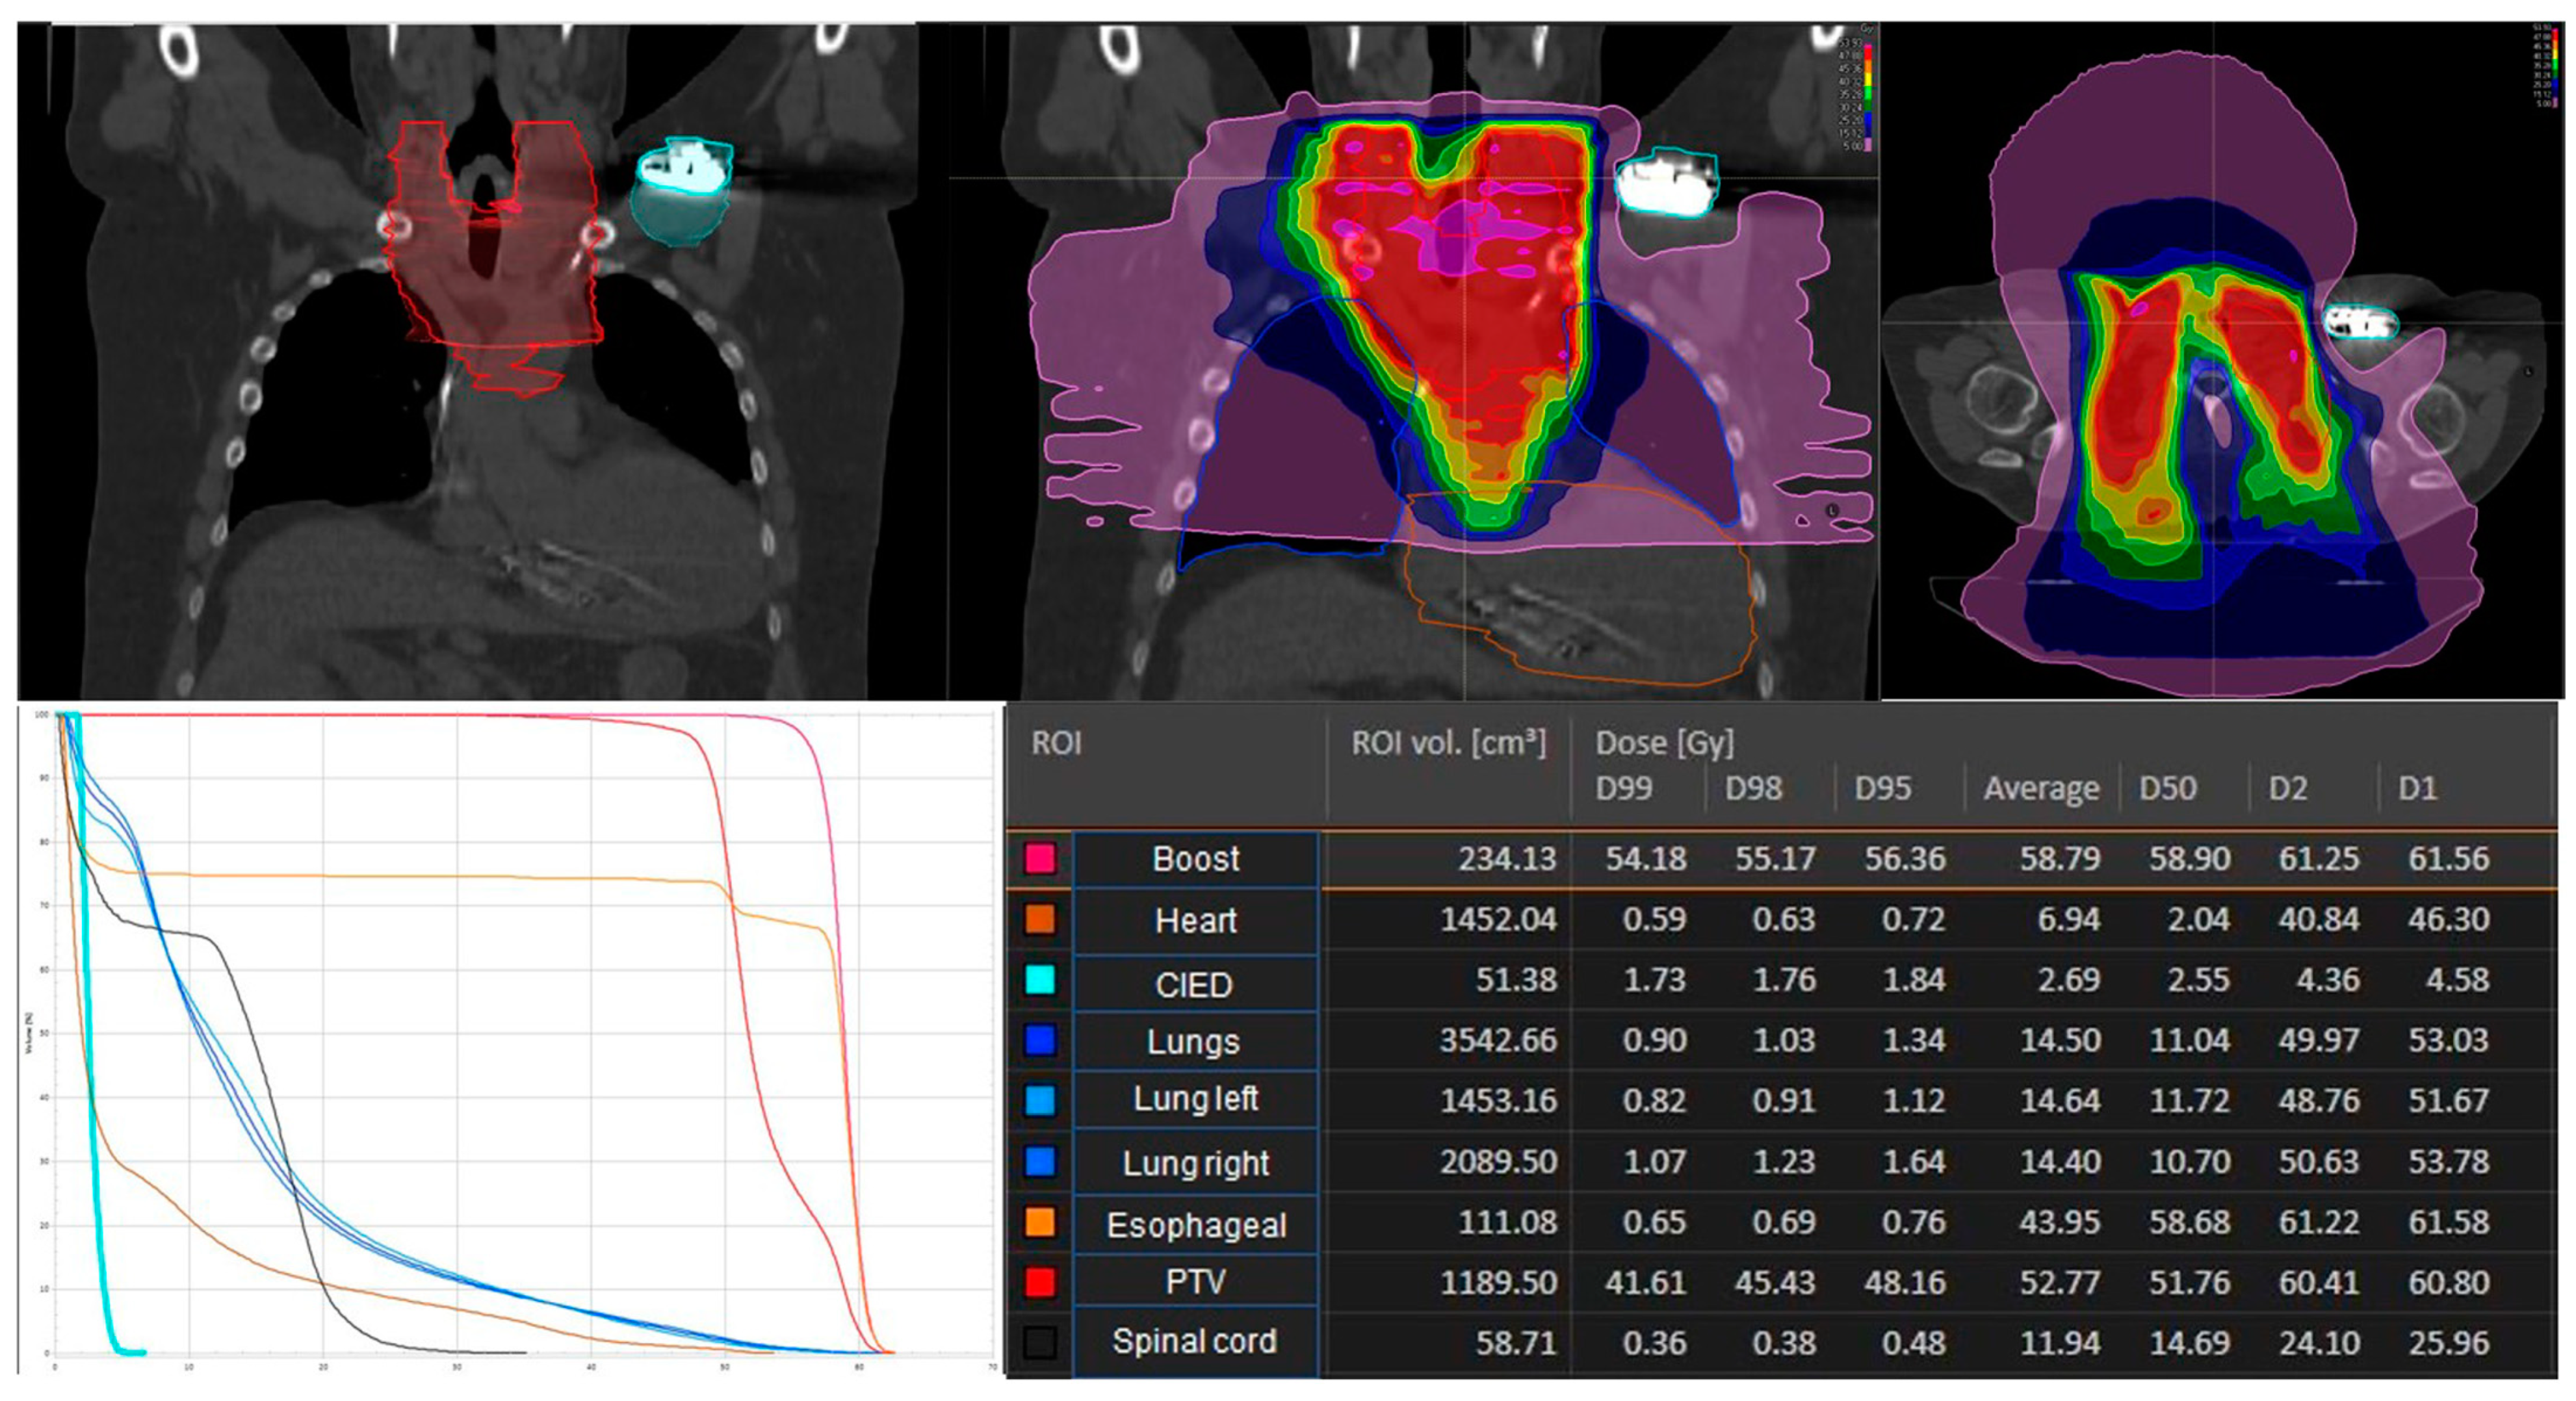

| RT-technique | |

| 3D-CRT | 1 (6.25%) |

| IMRT | 15 (93.75%) |

| Mean total dose PTV | 58.8 Gy (range:36.0–58.8 Gy) |

| irradiation cervical lymph nodes | |

| yes | 12 (75.0%) |

| No | 4 (25.0%) |

| Mean PTV-volume | 810 ccm (range 207–1539 ccm) |

| Mean total dose CIED | 1.75 Gy (range 0.2–4.81 Gy) |

| Mean total dose ICD | 2.2 Gy (range 0.96–4.81 Gy) |

| Mean total dose PM | 0.6 Gy (range 0.2–2.0 Gy) |

| PTV | 851 ccm (range 207–1539 ccm) |

| Uncertainties on planning dose values | 0.4% (range 0.1–2.1%) |